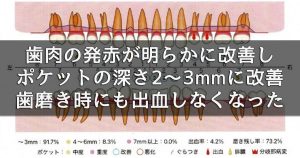

3週間後の再評価では、歯肉の発赤が明らかに改善し、腫れも引いてポケット深さは2~3 mmに改善。歯磨き時にも出血しなくなりました。

3週間後の再評価では、歯肉の発赤が明らかに改善し、腫れも引いてポケット深さは2~3 mmに改善。歯磨き時にも出血しなくなりました。